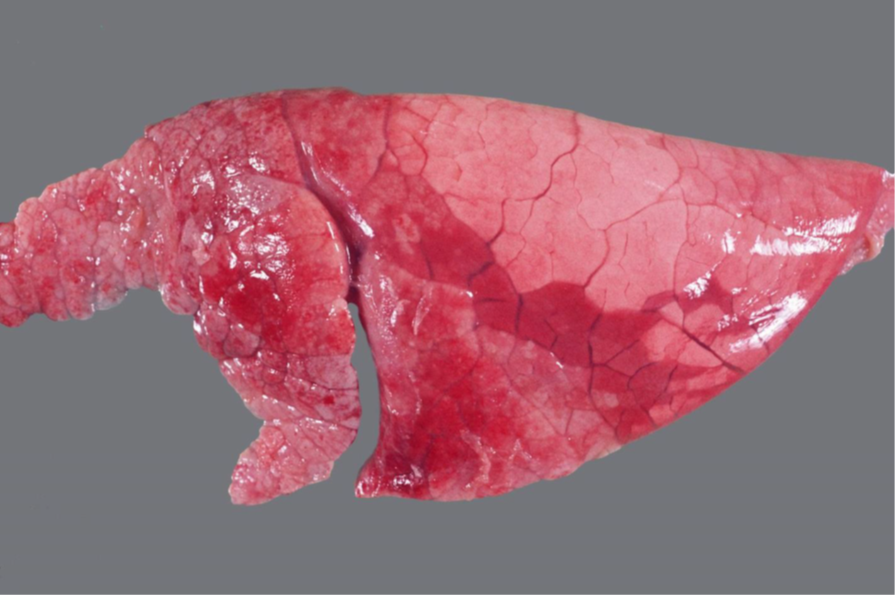

Rind, Lunge: hochgradige, subakute bis chronische, multifokale, embolisch-eitrige Pneumonie

Beschreibung:

- multiple, über das gesamte Parenchym verteilte, nahezu gleichgroße, gelbliche Herde mit deutlicher Abgrenzung zum angrenzenden hyperämischen Parenchym

- (daneben ein alveoläres und interstitielles Emphysem)

Hintergrundwissen/ Infektionsweg/ Pathogenese/Ätiologie

- Syn. embolisch-eitrig/metastatisch-eitrig

- hämatogene Streuung von bakteriellen Erregern aus einem extrapulmonalen (Primär-)Herd, im Rahmen

einer hämatogenen Streuung sind evtl. auch andere Organe betroffen (Septikämie > Niere, ZNS)

- vor allem bei Jungtieren mit ihrem noch nicht voll ausgebildeten Abwehrsystem, z.B. aus

Omphalophlebitis

- andere mögliche Primärherde: Klappenendokarditis, Leberabszesse, Mastitis, Klauenveränderungen

- zwei Formen kommen vor:

a) eitrige Einschmelzung mit typischer Abszessbildung

b) aggressive, schnellwachsende Bakterien führen zu hämorrhagisch-nekrotischen Herden

- typisch sind makroskopisch die multiplen, gleichgroßen Veränderungen, die über die "gesamte" Lunge

verteilt sind (Hinweis auf embolisch/metastatisch-eitrige Pneumonie nach hämatogener Streuung der

Erreger), im Gegensatz dazu bei der abszedierenden Pneumonie einzelne oder mehrere unregelmäßige,

konfluierende Herde! (als Komplikation einer katarrhalisch-eitrigen Bronchopneumonie nach aerogener

Infektion)

- häufig typische Eiter-Erreger: Rd/Sw: Trueperella pyogenes, Pf: Actinobacillus equuli, alle: E. coli